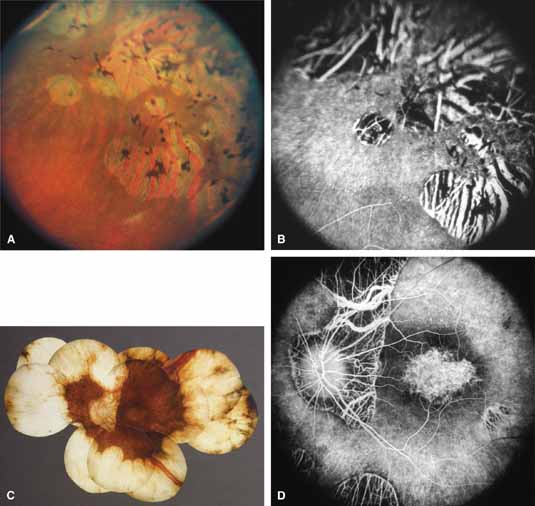

Choroideremia (gene symbol CHM; MIM No. 303100) is an X-linked disorder that is characterized by the onset of night blindness in the first or second decade of life followed by slowly progressive atrophy of the choroid and retina that usually results in legal blindness by midlife and near virtual blindness in later years. The disorder begins with a diffuse atrophic process involving retinal pigment epithelium and choriocapillaris (Figs. 12A, 12B, 12C, and 12D) but eventually results in near total vascular choroidal atrophy (Fig. 13A). The fundus does not show the sharp border or transition area that is characteristically seen with gyrate atrophy. The peripheral visual field is depressed and eventually becomes severely constricted. The ERG and EOG are abnormal early in the course of the disease.

Women who are carriers for choroideremia will nearly always show evidence of this on examination with patchy mottling and atrophy of the fundus with hyperpigmentation (Figs. 13B, 13C, and 13D). Random inactivation of one of the two X chromosomes, also called lyonization, results in the expression of the defect in a certain population of a carrier woman's retinal and choroidal cells, causing the carrier manifestations. These changes can occur in a patchy distribution throughout the fundus. Usually, carrier women are asymptomatic or, at most, experience only mild symptoms of poor night vision or pericentral scotomas, if the changes affect the posterior pole. Uncommonly, the carrier manifestations may cause considerable visual impairment, if the macular regions are involved. Histology has showed patchy loss of choroid, pigment epithelium, and photoreceptor outer segments, with abrupt transition from normal to abnormal areas.70 More diffuse abnormalities of the retinal pigment epithelium have been found throughout the fundus, suggesting that the defect may have a primary effect on this tissue.